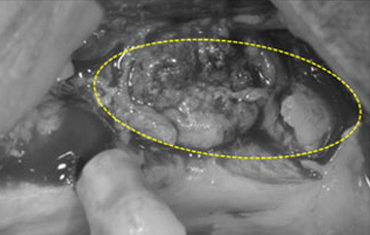

타 치과의 뼈 이식 후 골조직

램브란트치과 상인점 뼈이식 후 골조직